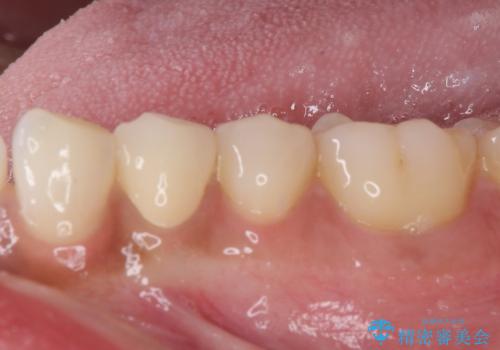

痛みでうずく 根管治療と補綴治療

- 下顎の小臼歯が食事などの度に痛みを感じるとのことで来院された患者様です。

レントゲン写真などで診査を行ったところ、左下の第一小臼歯の神経組織が壊死し、根尖部周辺の骨に炎症が認められました。

まずは根管治療を行い、症状が消退したことを確認してオールセラミッククラウンにて補綴治療を行うこととしました。

根管治療後6ヶ月でレントゲン写真を撮影したところ、根尖部周辺の炎症が消退していることが認められました。